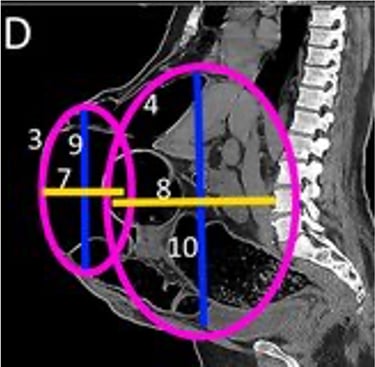

Realizamos una Tomografía Axial Computarizada con reconstrucción en 3D de la Pared Abdominal y de la hernia, cuando corroboramos que todo está listo, el siguiente paso es elegir el tipo de malla quirúrgica a colocar en la cirugía.